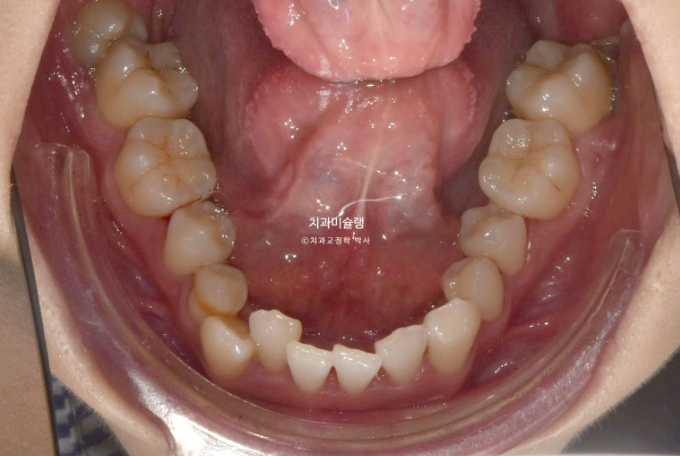

2년 전 덧니 교정치료를 위해 내원한 환자분입니다.

중심선 문제, 블랙트라이앵글, 과개교합, 반대교합, 가위교합 등이 보입니다.

발견되는 부정교합의 종류들을 나열해보자면

중심선 불일치

과개교합

대구치 가위교합

심한 덧니

전치부 반대교합

부정교합은 아니지만 블랙트라이앵글

정도가 되겠습니다.

이 정도라면 작은어금니 4개 발치교정 진단을 할만도 하지만

입술 돌출이 없고 입술이 얇아 발치교정이 고민되는 상황입니다.

결국 환자분과 논의 후 입매 변화 없는 비발치로 진행하기로 합니다.